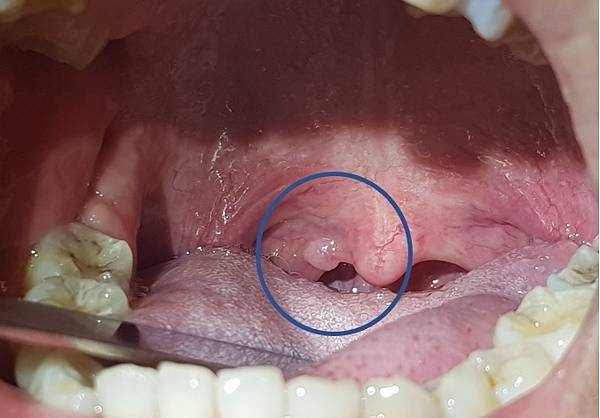

一位20出頭年輕美眉,到我的門診就醫,因為她被其他醫師告知,喉嚨裡面長了東西,希望能尋求幫助。

她很擔心,怎麼這麼年輕就得到腫瘤。經過詳細檢查,發現在她的懸壅垂(俗稱小舌或喉嚨滴ㄚ),有一個小小的腫塊,於是直接在門診幫她切除,並送化驗。